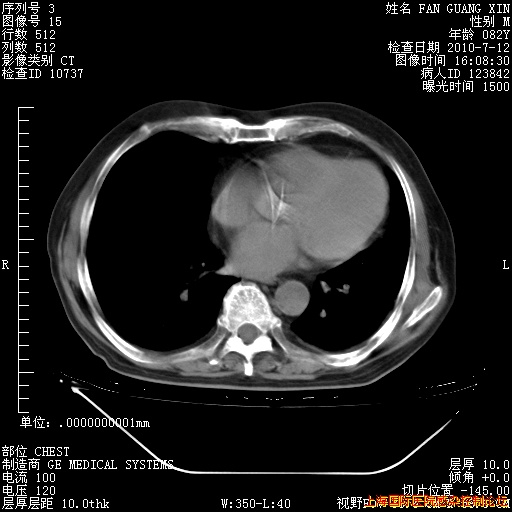

6月12日纵膈窗

整整相隔30天的肺部CT好像有所好转啊。甲强龙减量第3天,需要观察体温。

海管,自昨日你和我通完话后,不知您岳父消化道症状有无缓解?体温怎样?阅读7.12日胸部ct,个人认为目前激素治疗是有效的,甲强龙减量是适宜的。因在抗痨治疗,需密切观察肝功、肾功能和血常规。不过,老年、长期住院和大量使用激素,很担心菌群失调发生